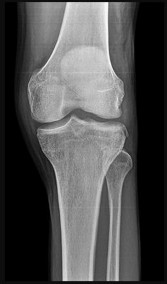

Which bundle of the posterior cruciate ligament (PCL) is the primary restraint to posterior tibial translation at 90 degrees of knee flexion?

Correct Answer: Anterolateral bundle

Explanation:

The PCL has two main bundles: the anterolateral (AL) and posterolateral (PL) bundles. The AL bundle is larger, tighter in flexion, and acts as the primary restraint to posterior tibial translation at 90 degrees of knee flexion. The PL bundle is tighter in extension. Reconstructing the AL bundle is the primary goal in single-bundle PCL reconstruction.